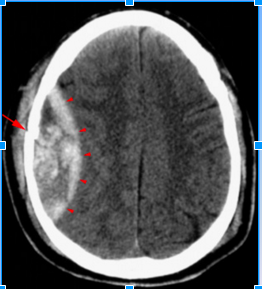

High density, crescent shaped hematoma (arrowheads)

overlying the right cerebral hemisphere. Whats important to note in this image?